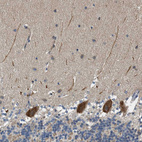

Immunohistochemical staining of human cerebellum shows strong cytoplasmic positivity in Purkinje cells.